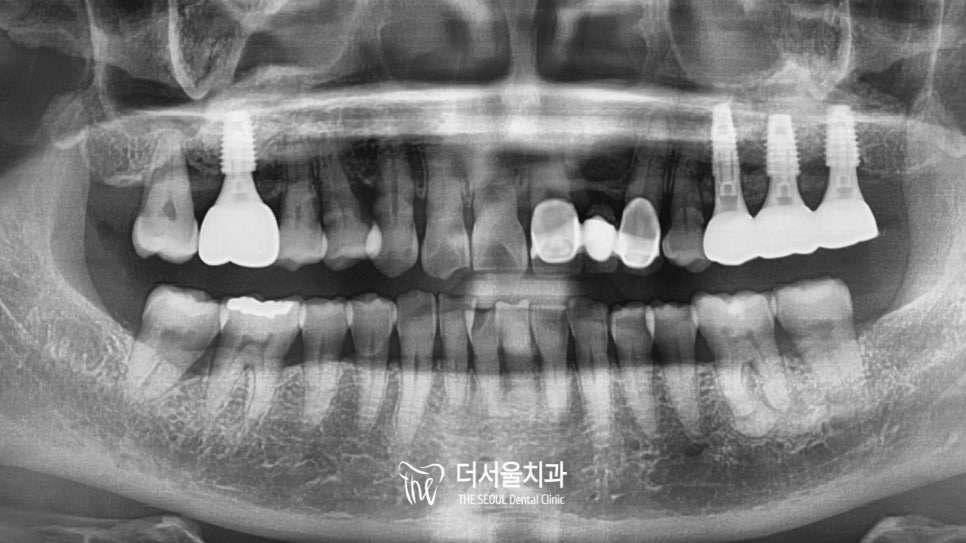

파노라마로 완성된 모습을 확인해보니

형태는 물론이며, 기존 조직 및 치아와도

조화를 잘 이루고 있는데요.

크기도 알맞게 제작되어

저작 기능을 하는데에도

문제가 없어 보입니다.

구강 내를 살펴보니

이전에 비해 훨씬 건강해보이네요ㅎㅎ